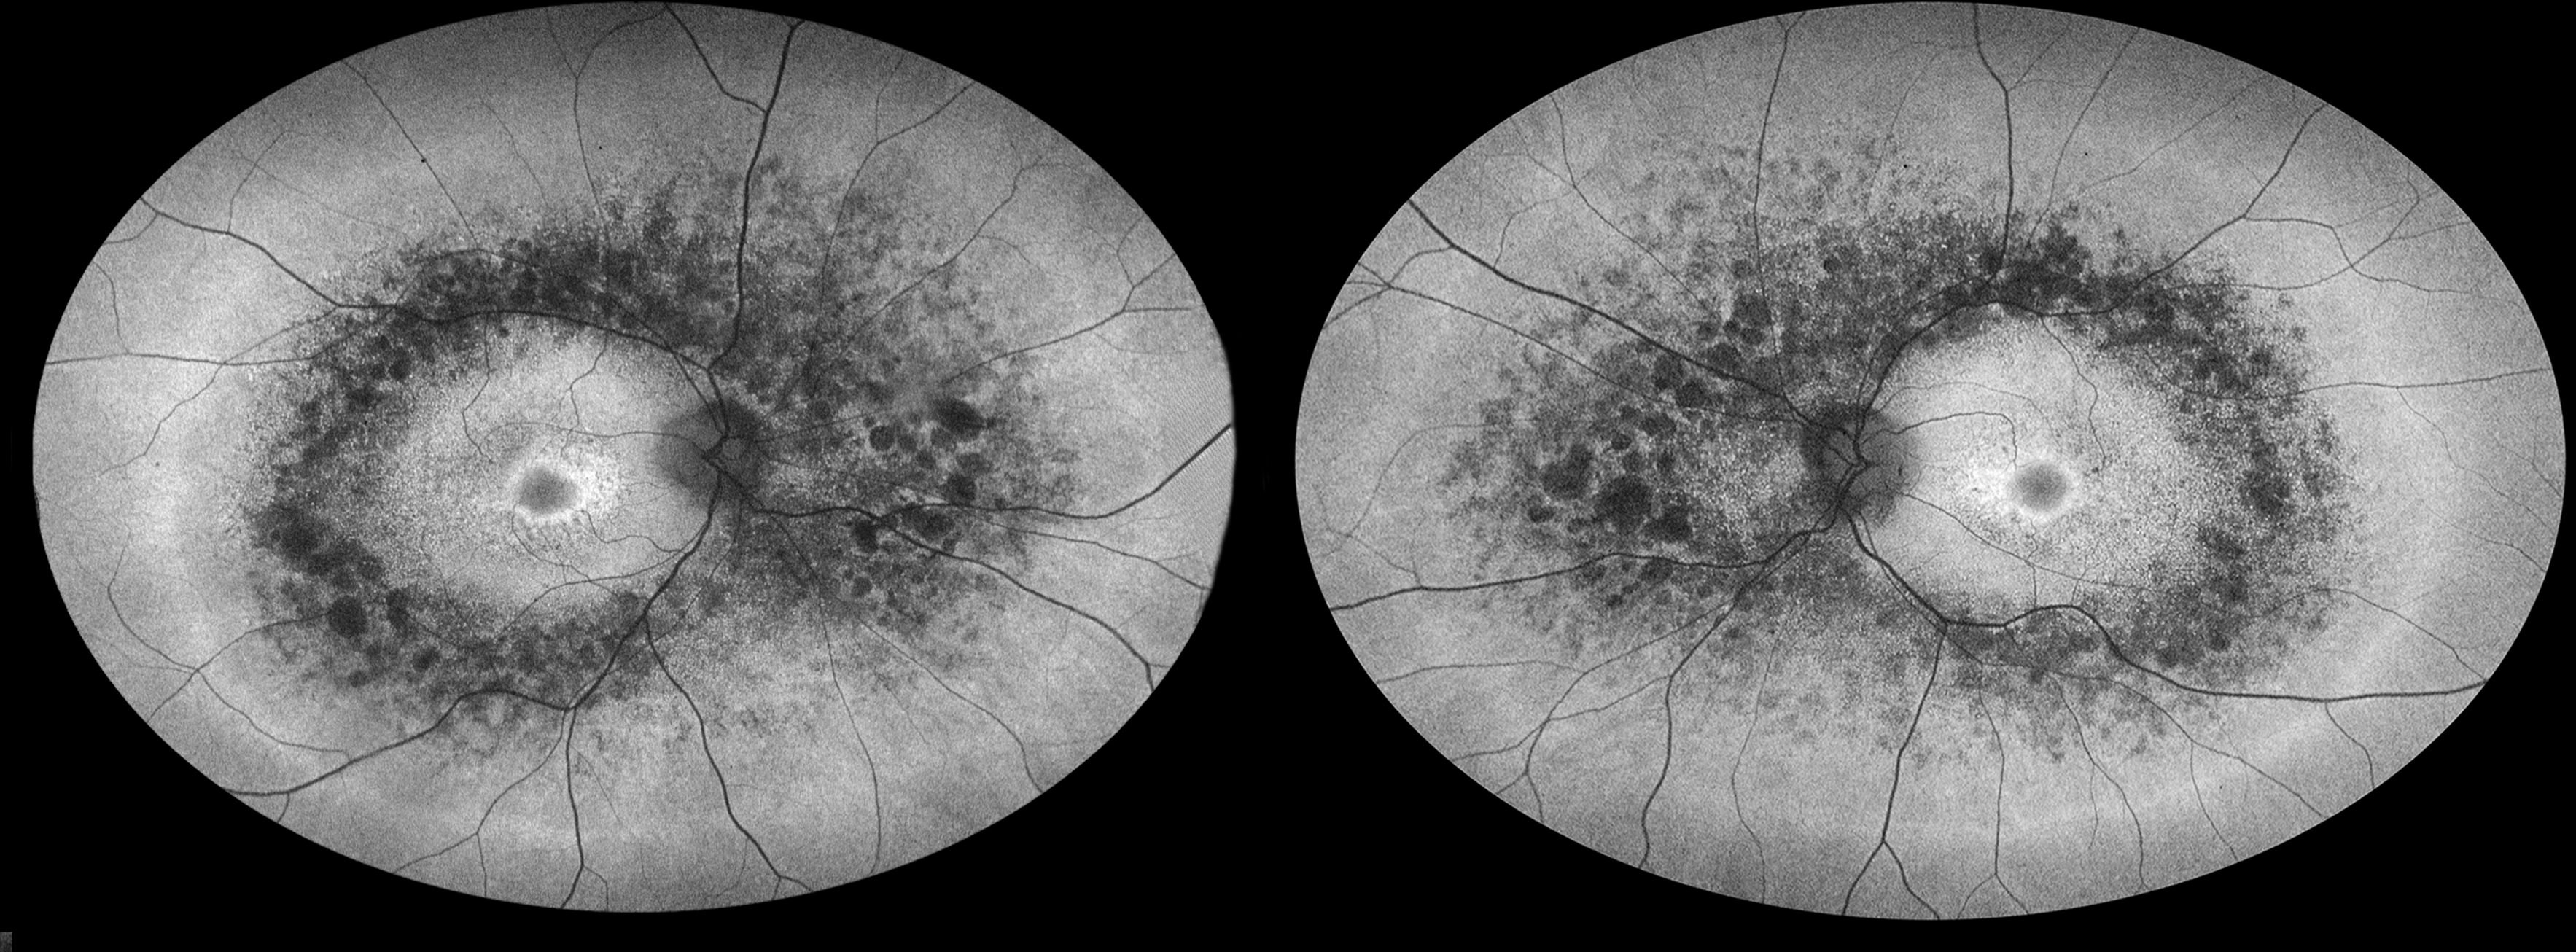

RP Presented by Judith Gulian, OCT-C This photograph received Second Place, Autoflourescence in the 2025 OPS Scientific Exhibit. Filed Under Retina OPS Photo